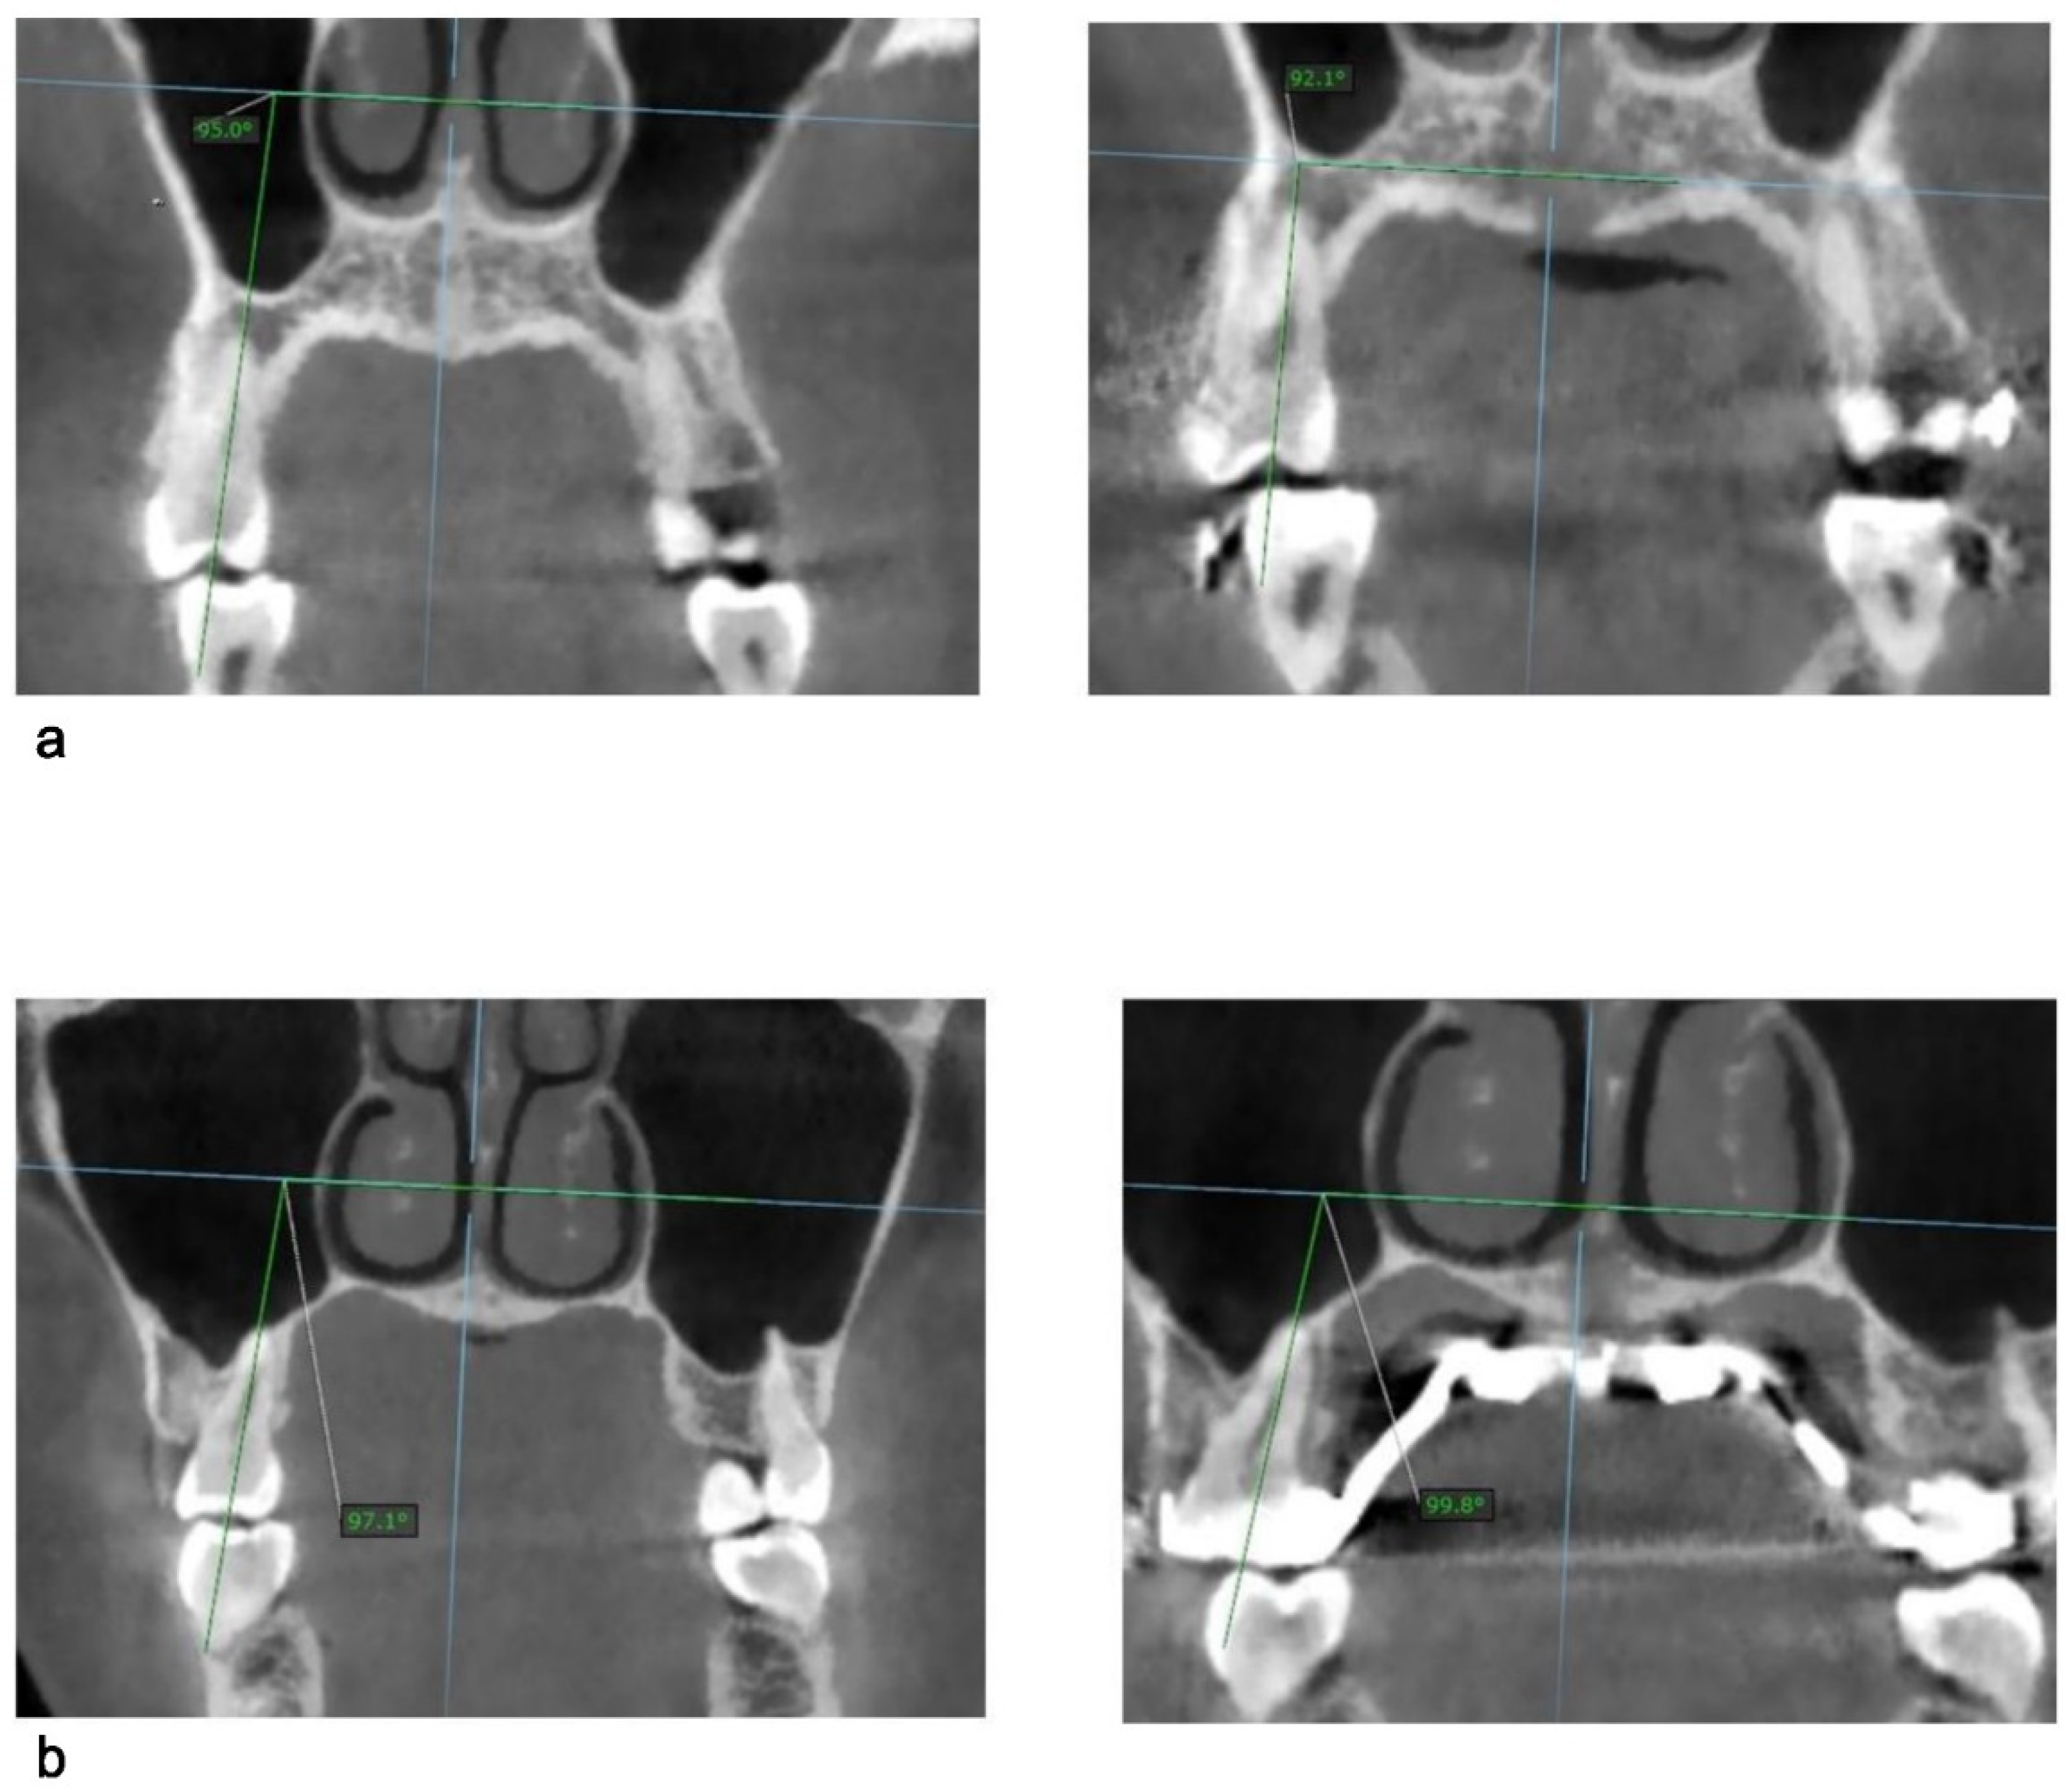

| Tooth No | Pre-Expansion | Post-Expansion | Change | p Value |

|---|---|---|---|---|

| 14 | 91.8 ± 11.1 | 91.2 ± 10.4 | −0.6 ± 2.7 | 0.27 |

| 24 | 95.0 ± 9.1 | 94.7 ± 9.1 | −0.4 ± 1.8 | 0.23 |

| 15 | 92.0 ± 7.6 | 92.6 ± 7.4 | 0.6 ± 1.9 | 0.17 |

| 25 | 92.3 ± 12.4 | 93.7 ± 12.5 | 1.5 ± 1.7 | 0.018 * |

| 16 | 108.0 ± 6.5 | 110.8 ± 6.2 | 2.8 ± 2.4 | 0.0002 * |

| 26 | 110.3 ± 7.3 | 113.8 ± 7.9 | 3.5 ± 2.1 | <0.0001 * |

| 17 | 114.7 ± 7.5 | 116.6 ± 7.3 | 1.9 ± 2.4 | 0.004 * |

| 27 | 114.6 ± 7.8 | 116.8 ± 8.5 | 2.2 ± 2.6 | 0.0008 * |